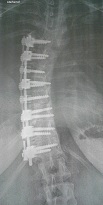

Nachdem bei mir mit 8 eher zufällig eine Skoliose entdeckt wurde (war im Winter ausgerutscht und auf den Rücken gefallen - Brustwirbel angebrochen, 18° in der Hauptkrümmung), habe ich mit 9 mein erstes Korsett bekommen, da waren es schon 28°. Nach einem falschen Korsett, einem Arzt- und Sanitäthauswechsel, einer Kur in Bad Elster mit 13 und einer täglichen Korsett-Tragezeit von 15-17 Stunden sowie Physiotherapie kam ich dann mit 14 (2002) trotzdem nicht mehr um eine OP drumrum. Ich hatte ohne Korsett 68°. Unsere Orthopädin schickte uns nach Cuxhaven, um dort Informationen zu einer OP zu bekommen. Es wurde uns erzählt, dass wir bald mit Lähmungserscheinungen zu rechnen hätten und im schlimmsten Fall die Wirbelsäule brechen könnte, wenn die Gradzahl weiter so rasant ansteigt. Es wurden noch die Hände und die Beckenkämme geröntgt, damit sicher war, ob ich ausgewachsen bin. Und dann ging’s im Oktober 2002 ins Seehospital Sahlenburg.

Ich hab auch mal ein paar Bilder für euch. So viel von mir